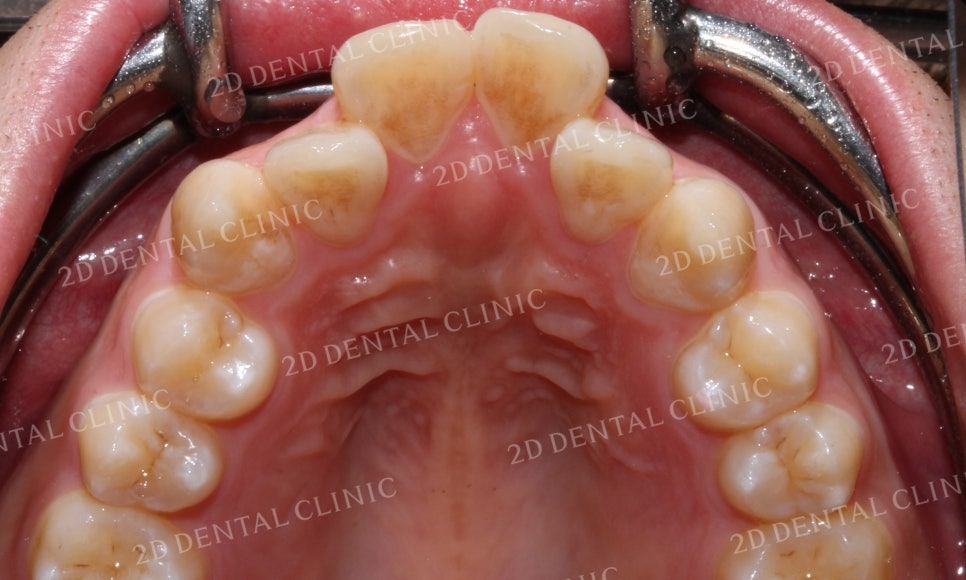

상악의 설측면 사진입니다.

발달된 구강의 구조가

전치로 가면 갈수록 좁아지는

V-Shape을 띠고 있습니다.